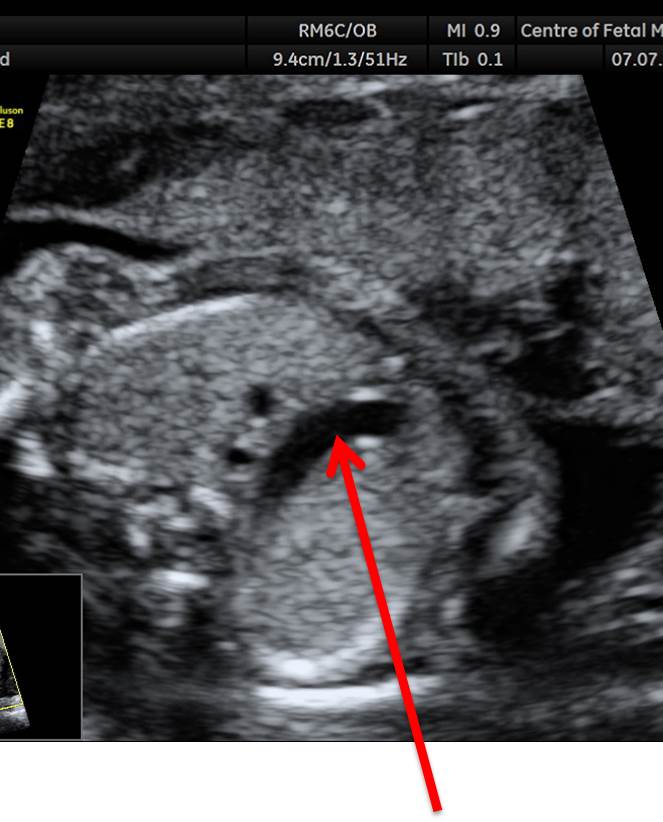

Вопрос 12

Поставьте диагноз

• А — норма;​

• Б — АВ-канал ;​

• В — коарктация аорты;

• Г — гипоплазия левого желудочка

Ответ на вопрос 12

• На 4камерном срезе сердца мы видим диспропорцию правого и левого желудочка с относительным уменьшением левого желудочка. Кровоток через митральный клапан сохранен, что позволяет исключить атрезию митрального клапана и гипоплазию левого желудочка

• В срезе через дугу аорты и дугу артериального протока мы видим, что перешеек аорты значительно меньших размеров по сравнению с артериальным протоком, что позволяет установить коарктацию аорты